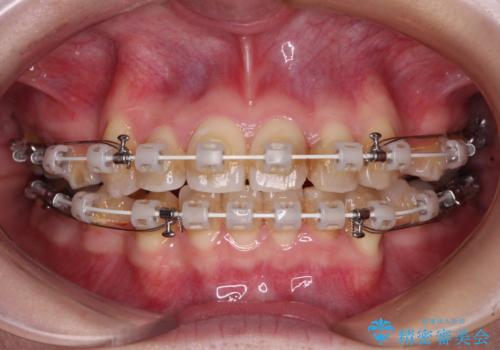

- 矯正装置

- 審美装置

- 上下の八重歯と前歯のデコボコを気にして来院された患者様です。

右上と左下の八重歯が特に著しく、上顎正中が右側にシフトしていました。

デコボコが強いため小臼歯4本を抜歯し、上顎正中を左側に移動させるために補助装置を使用して、ワイヤー装置にて矯正治療を行うこととしました。

八重歯のためずれていた上下の正中をほぼ一致する位置に整えることができました。

重なって汚れの溜まりやすかった部分も改善され、大変満足していただけました。